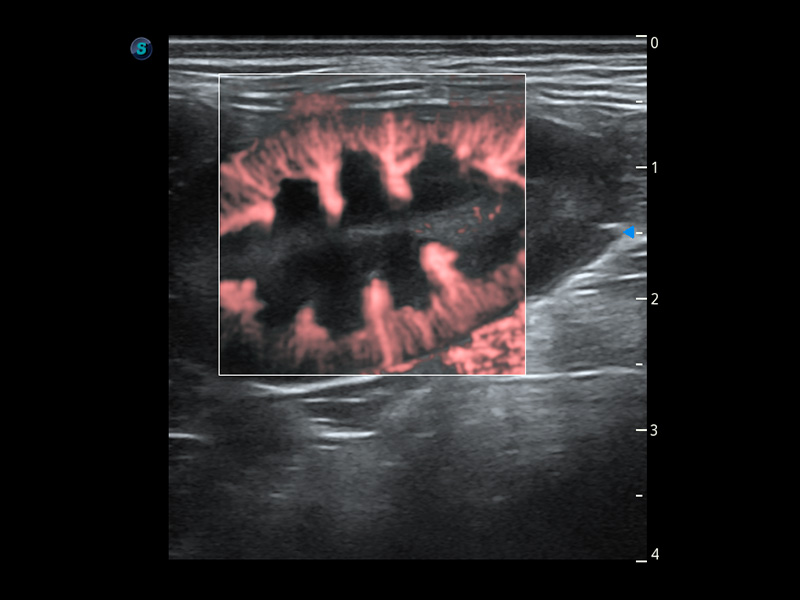

4T血流成像 微察秋毫

融合不同血流成像技术的优势,即可以提升血流成束性,同时可提高血流的视觉敏感性。

PDI 能量多普勒血流

提供高灵敏度和空间分辦率的血流图像,获得更加真实和丰富的诊断信息。

SR Flow 高分辨率血流成像

能够清晰显示细小、低速血流图像,获取传统彩色多普勒技术难以得到的细节和信息。

Micro F 显微血流成像

通过创新的Matrix E自适应滤波器和超长时间域算法,极大提升超低速微细血流的检出能力,同时更精准地滤除软组织和噪声信号,为兽用医生提供以往无法通过常规血流获得的疾病诊断信息。

Bright Flow 立体血流成像

在传统二维血流成像的基础上,呈现血流的立体感,具有动感的生命力之美。精确区分不同血管的空间关系,提高了血流的视觉敏感性。

优异的基础图像

(犬)肾脏血流